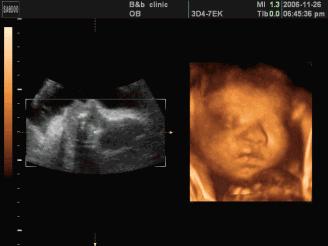

5D四维彩超是

一种全面的

排畸检查

这是普通彩超无法比拟的

怀孕二十多周之后就可以做5D四维彩超了,但是最佳的时候是22~24周,这个时期胎儿的肢体和主要器官已经全部发育,而且羊水量较多,在宫内的活动空间较大,采集的图像比较,适合做胎儿畸形筛查。

过去B超只能检查胎儿的生理指标,而四维彩超可以准确的提供有关胎儿大小、羊水多少、脐带是否绕颈的信息,而且检测胎儿先天缺陷的精确度更高,如唇裂,脊柱裂,大脑、肾、骨骼发育不良等,为早期诊断胎儿先天性体表畸形提供准确科学依据。

5D四维彩超排畸检查的准确度与设备有很大关系,睢宁东方医院斥巨资引进先进三星麦迪逊WS80A   5D四维彩超,其高清细腻的画面,逼真的立体成像,呈现出更真实、更详细的胎儿图像,提高临床诊断的准确性。

5D四维,能自动为胎儿进行宫内拍“写真”和动态录像,为准妈妈增添了不少情趣。她们不再是仅仅感觉宝宝运动,而且可以亲眼目睹肚子里宝宝的乖巧容貌和可爱动作。